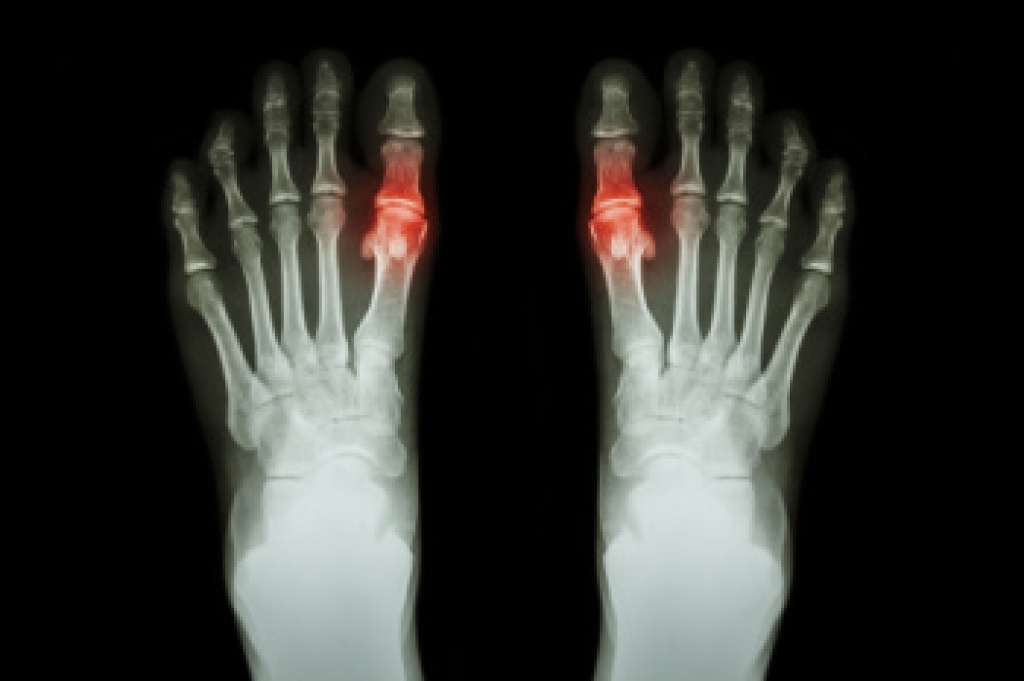

Risks and Causes of MTP Joint Pain

The toes are connected to the long bones of the foot with metatarsophalangeal, or MTP, joints. These joints are essential for balance and forward motion while walking. Pain in this area, most often in the big toe, develops when the joint is exposed to excess stress, poor alignment, or conditions that cause inflammation. Common causes include bunions, turf toe, and certain forms of arthritis like gout, osteoarthritis, and rheumatoid arthritis. MTP joint problems can lead to swelling, stiffness, and tenderness that make it difficult to walk or stand comfortably. Risk factors include chronic inflammatory disease and foot or leg misalignment. Wearing shoes that lack adequate support or place pressure on the toes, such as high heels or narrow footwear, are other factors. A podiatrist can assess the underlying cause and provide effective treatment to reduce pain and improve alignment. If you have ongoing pain in an MTP joint, it is suggested that you make an appointment with a podiatrist for an exam and treatment options.

What Causes Toe Pain?

Toe pain can be caused by one or more ailments. The most common include:

- Trauma

- Sports injury

- Wearing shoes that are too tight

- Arthritis

- Gout

- Corns and calluses

- Hammertoe

- Bunions

- Blisters

- Ingrown toenails

- Sprains

- Fractures (broken bones)

- Dislocations

In many cases the cause of toe pain is obvious, but in others, a podiatrist may want to use more advanced methods to determine the problem. These can range from simple visual inspections and sensation tests to X-rays and MRI scans. Prior medical history, family medical history, and any recent physical traumatic events will all be taken into consideration for a proper diagnosis.

Treatments for toe pain and injuries vary and may include shoe inserts, padding, taping, medicines, injections, and in some cases, surgery. If you believe that you have broken a toe, please see a podiatrist as soon as possible.